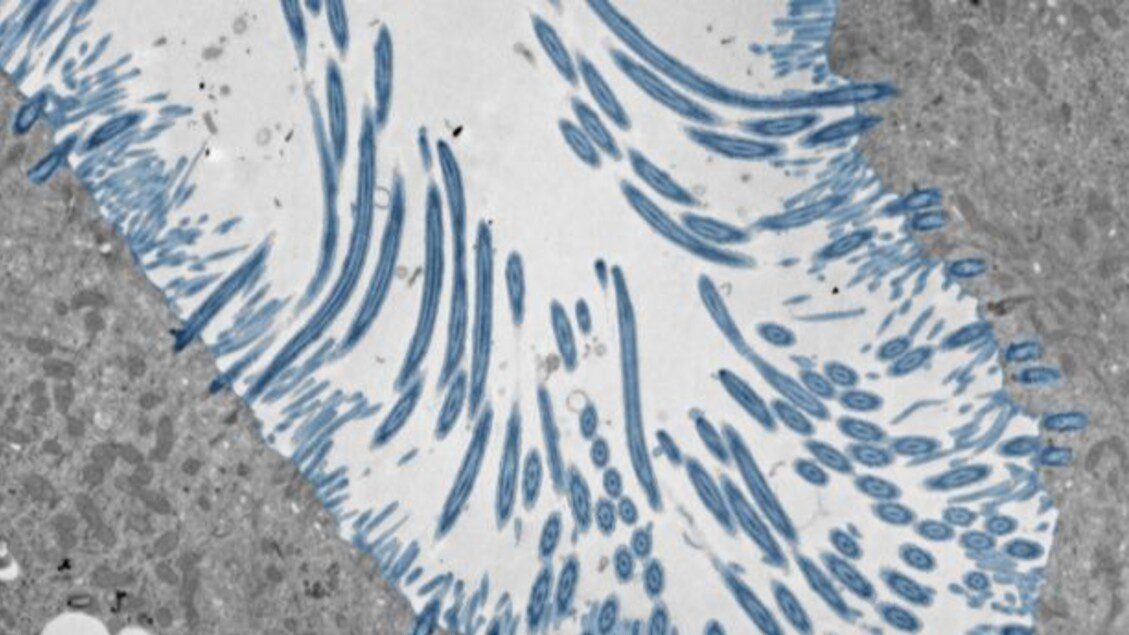

Grazie all’organoide ottenuto in laboratorio, i ricercatori coordinati da Ellen Foxman hanno potuto osservare la risposta coordinata di migliaia di cellule contemporaneamente. Quando rilevano la presenza del rinovirus, infatti, le cellule iniziano a produrre interferoni, proteine che bloccano l’ingresso del virus e la sua replicazione. La difesa non coinvolge solo le cellule infettate, ma anche tutte quelle vicine, e se si svolge abbastanza rapidamente il virus non riesce a diffondersi. Il ruolo cruciale di questo meccanismo è stato dimostrato quando gli autori dello studio lo hanno bloccato: il rinovirus ha rapidamente infettato moltissime cellule, causano in alcuni casi addirittura la morte degli organoidi.

Se l’attacco del virus è più massiccio vengono poi attivate anche altre ‘armi’, come l’aumentata produzione di muco e una risposta infiammatoria. “I nostri esperimenti dimostrano quanto sia fondamentale ed efficace una rapida risposta dell’interferone nel controllo dell’infezione da rinovirus – commenta Bao Wang, primo autore dello studio – anche in assenza di cellule del sistema immunitario”.